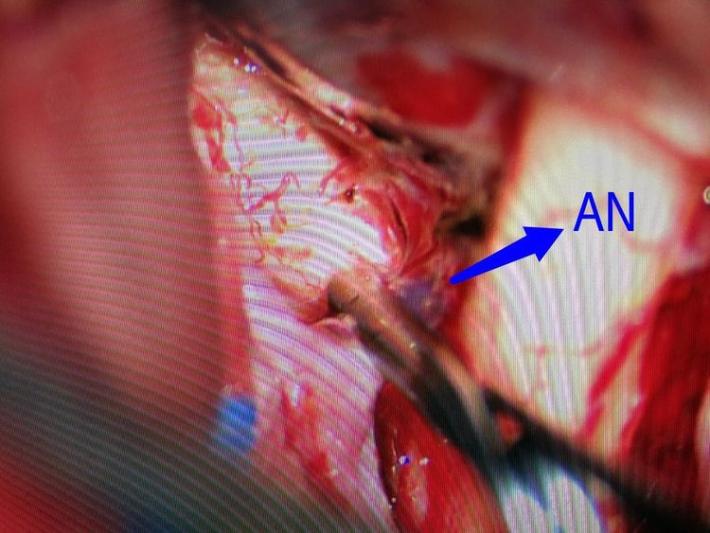

右侧翼点入路,解剖脑池系统,见前交通动脉瘤向右前伸入右侧视神经下方。予以夹闭。

显露诸血管正常。

探查右脉前小动脉瘤,未破,予以包裹。手术完毕。